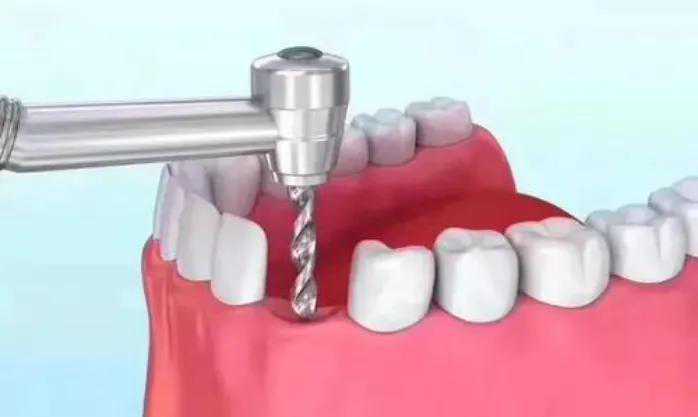

step2.

正式开始种植牙手术。在牙槽骨上制备一个孔,植入人工种植体。将牙骨床内严密缝合,大约一个星期后可以拆线。这次大概2个半月--3个月)